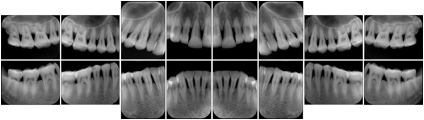

Intra-oral radiography typically involves acquisition of multiple images of various parts of the dentition. Many digital radiographic systems offer customized templates that are used for displaying the images in a study on the screen. These templates may also be referred to as mounts or view sets. The Structured Display Object represents a standard method of encoding and exchanging the layout and intended display of Structured Displays. A structured display object created in this manner could be stored with a study and exchanged with images to allow for complete reproduction of the original exam.

1. A patient visits a General Dentist where a Full Mouth Series Exam with 18 images is acquired. The dentist observes severe bone loss and refers the patient to a Periodontist. The 18 images from the Full Mouth Series along with a Structured Display are copied to a DICOM Interchange CD and sent with the patient to see the specialist. The Periodontist uses the CD to open the exam in his Dental Radiographic Software and consults via phone with the General Dentist. Both are able to observe the same exam showing the images on each user's display using the exact same layout.

Intra-oral Full Mouth Series Structured Display

Figure OO-1. Intra-oral Full Mouth Series Structured Display